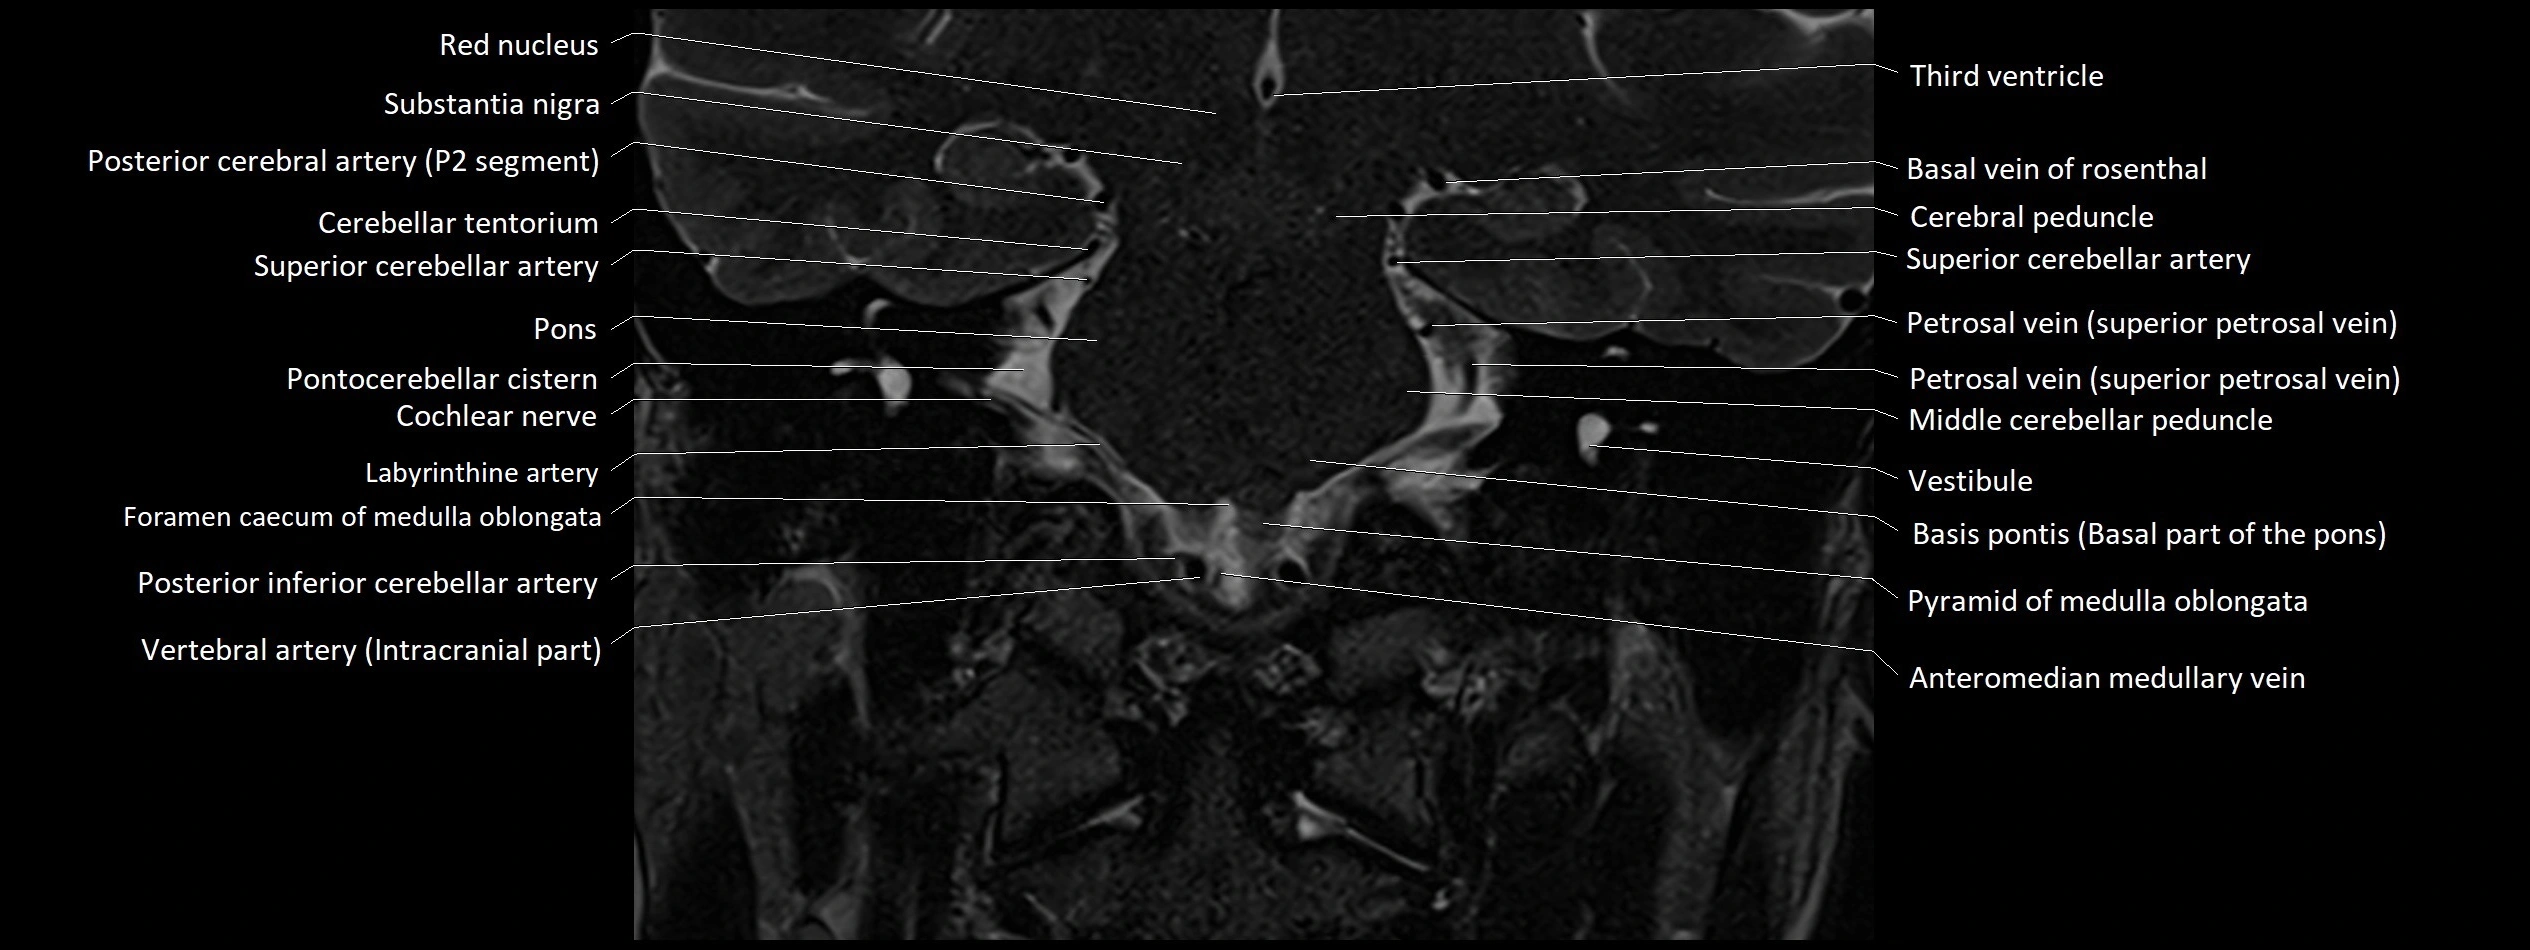

- Pontocerebellar cistern

- Middle cerebellar peduncle

- Petrosal vein

- Posterior inferior cerebellar artery

- Inferior petrosal sinus